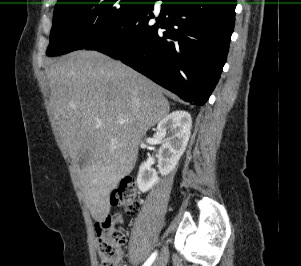

Мультиспиральная компьютерная томография (МСКТ) брюшной полости и забрюшинного пространства относится к современным лучевым методам исследования, с помощью которого можно оценить состояние органов брюшной полости (печени, желчного пузыря, поджелудочной железы, селезенки), забрюшинного пространства с расположенными в нем почками, надпочечниками, мочеточниками и прилегающих к ним кровеносных сосудов и лимфатических узлов.

С помощью мультиспиральной компьютерной томографии проводятся послойные рентгеновские снимки исследуемой области с толщиной среза от 0,5 мм. Затем полученные данные преобразуются в цифровые трехмерные модели органов и систем в мельчайших подробностях.

При подозрении на опухоли, воспалительные процессы, гнойные очаги назначается КТ брюшной полости и забрюшинного пространства с внутривенным болюсным контрастированием. Для этого пациенту внутривенно вводится рентгеноконтрастное вещество на основе йода. Благодаря усиленному кровоснабжению, которое обычно наблюдается в патологических очагах, препарат накапливается в структуре патологических образований и помогает врачу-рентгенологу выявить изменения внутренних органов.

Метод контрастирования помогает максимально точно выявить очаг патологии уже на начальной стадии, а также установить его локализацию, точные размеры, форму и особенности кровоснабжения. Возможности мультиспиральной компьютерной томографии позволяют выполнить своевременную диагностику заболеваний внутренних органов, от чего напрямую зависит эффективность лечения.